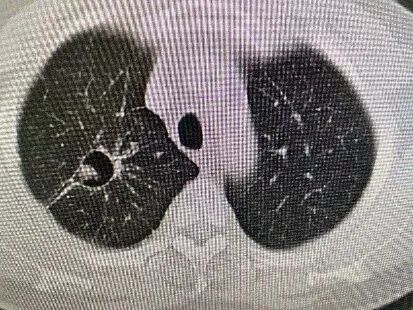

病理结果证实为肺腺癌,术后3个月复查CT:病灶已经逐渐吸收形成空洞了,就像在肺里留下了一道“烫伤疤痕”。

图片

治疗前dCJ帝国网站管理系统

射频消融后1天dCJ帝国网站管理系统

射频消融后2个月dCJ帝国网站管理系统